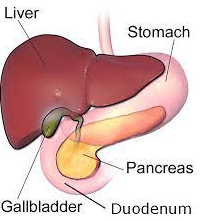

Often as we perform sonographic evaluation of the gallbladder and aorta, we pass over the pancreas and stomach, giving little consideration for the surrounding organs. In the world of anesthesiology, there has been a recent interest in using POCUS for assessing gastric contents in the perioperative period for patients taking a GLP-1 agonist for treatment of diabetes and obesity management to determine the incidence of retained gastric contents despite standard pre-operative fasting protocols.

Flynn et al. conducted a narrative review of the anatomy of the stomach and adjacent organs, exploring how ultrasound can be utilized to assess gastric content and predict the risk of pulmonary aspiration of gastric contents.